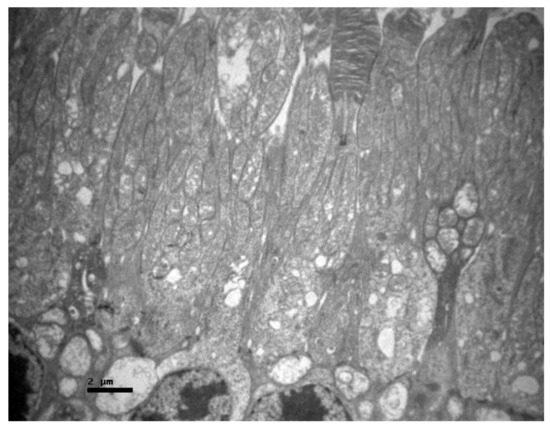

2.1. Group C

2.2. Group V

2.3. Group M